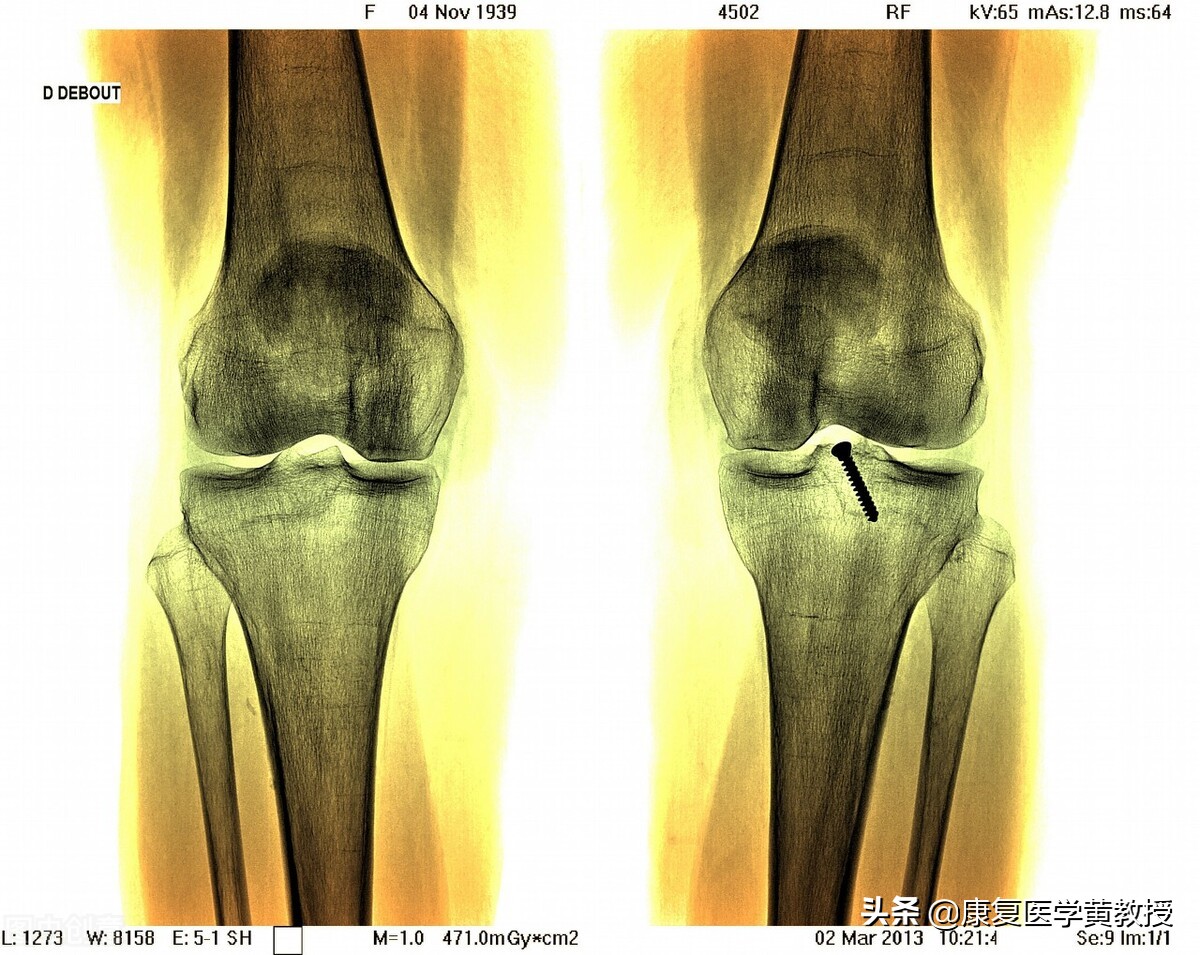

膝关节非常複杂,黄教授不厌其烦地一直发表与膝关节相关的观念与治疗,其实就是希望大家不要等到膝关节疼了才去治疗,因为膝关节一旦出现疼痛,只要去医院做检查,其实膝关节的结构都有程度不一的损伤与破坏,这其中最重要的是 软骨与半月板 ,这两套缓震系统如果失去功能,那麽膝关节就是一步步走入退化的深渊.虽然现在膝关节置换的材质先进,技术也完美,但侵入性治疗其实就是破坏人体的完整性, 因为膝关节发生退变,50%的原因并不在膝关节本身,膝关节置换手术解决的是膝关节结构的问题,但是脊柱,骨盆,髋关节与踝关节, 才是决定膝关节能力的重要伙伴啊!如果问题是踝关节,病变发生在膝关节,你该怎么办??